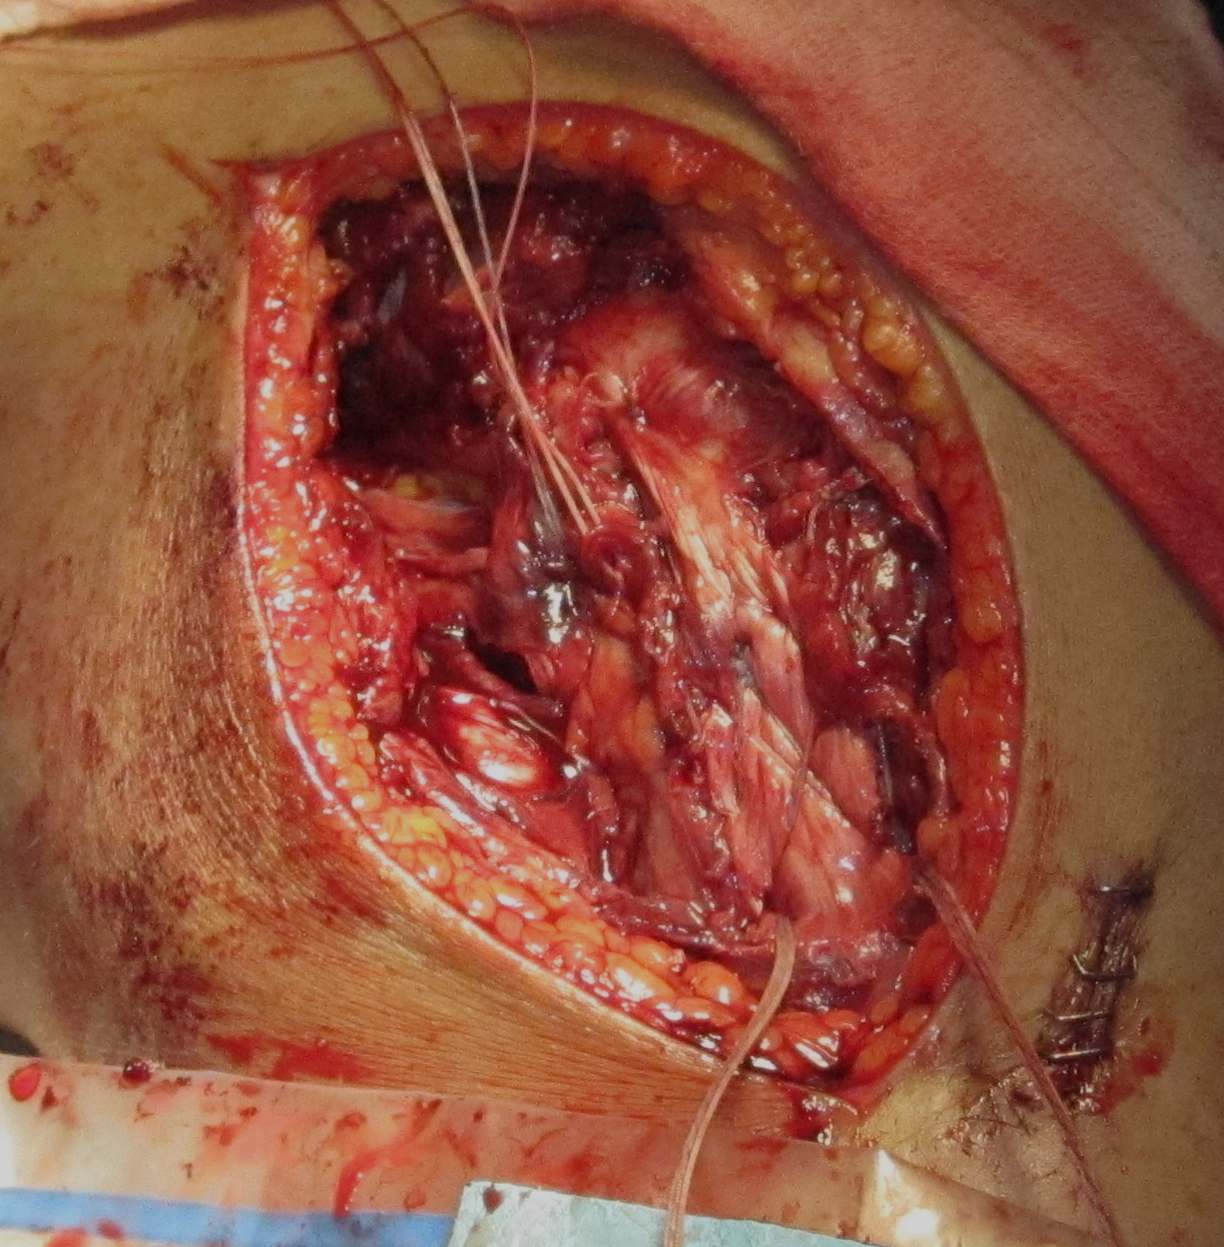

Surgical Approach to Medial Knee

Position

- knee flexed to 90o, over bolster

- tourniquet

- sandbag under hip

Incision

- hockey stick medial incision

- halfway between borders of tibia

- extends proximally to adductor tubercle

- distally to pes anserinus

Superficial dissection

- protect the saphenous nerve and small saphenous vein

- emerges from between sartorius and gracilis

- divide medial patella retinaculum from VMO down

- divide sarfascia over pes anserinus

- reflect pes anserinus inferiorly

Deep dissection

- elevate VMO to identify proximal insertion of superficial MCL

- expose superficial MCL running from medial epicondyle down to tibia under pes

- popliteal oblique ligament and semimembranosus are posterior to MCL

- can expose posterior capsule by carefully reflecting medial gastrocnemius posteriorly